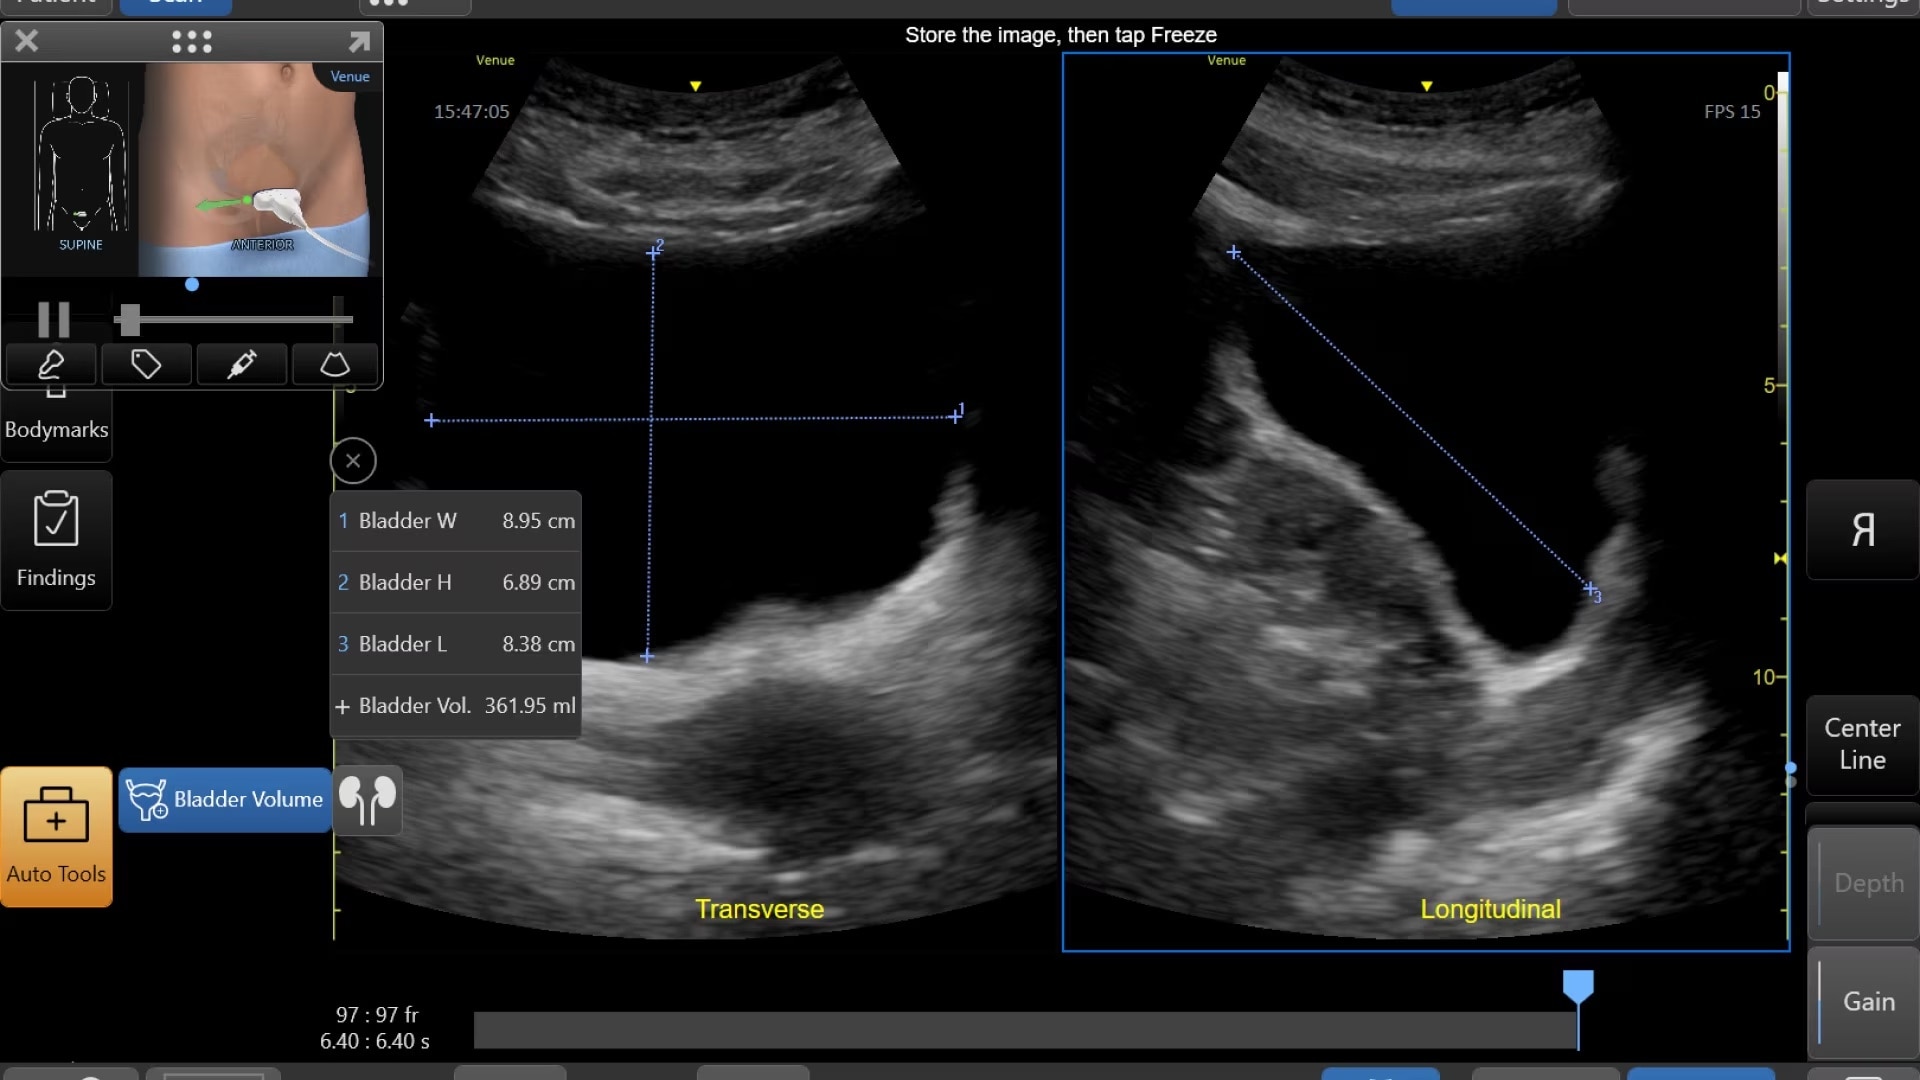

Quickly assess kidneys and the bladder with Renal Diagram

Simplify documentation and provide easy follow up for patients with suspected hydronephrosis. No need to type findings; simply assign a label from a pre-populated list that correlates with images.